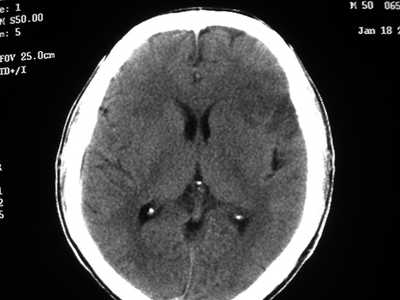

以下是引用卜一在2007-1-19 15:29:00的发言:[br]治疗前:1月14日右侧额叶皮质下低密度影,而治疗后:1月18日右侧阴影消失,新近出现左侧额叶侧脑室前角旁大片状低密度影,边缘模糊。支持—双侧额叶后部缺血性脑梗塞。